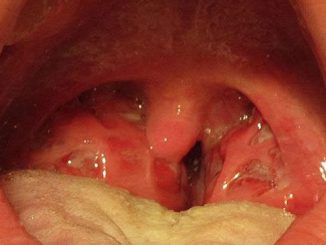

gnojna angina

Gnojna angina: simptomi, prenošenje, lečenje, trajanje

April 17, 2018 simptomibolesti 0

GNOJNA UPALA GRLA, poznatija kao gnojna angina, je češća kod dece nego kod odraslih, mada se svakako može javiti i kod starijih ljudi. Gnojna angina […]